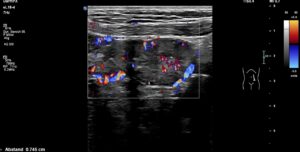

The pain was located to the left of the umbilicus when standing. Here, increased perfusion of the small bowel was observed, which disappeared when the patient lay down. A substantial swelling of the jejunal wall to 7 mm in the area left of the umbilicus was eye-catching .

Massively swollen (7,5 mm, normal up to 2 mm) painful (palpation under sonographic guidance) jejunal loop with hyperperfusion

The thickened wall was significantly hyperperfused. Winding mesenteric veins could be seen running towards the thickened bowel loop.